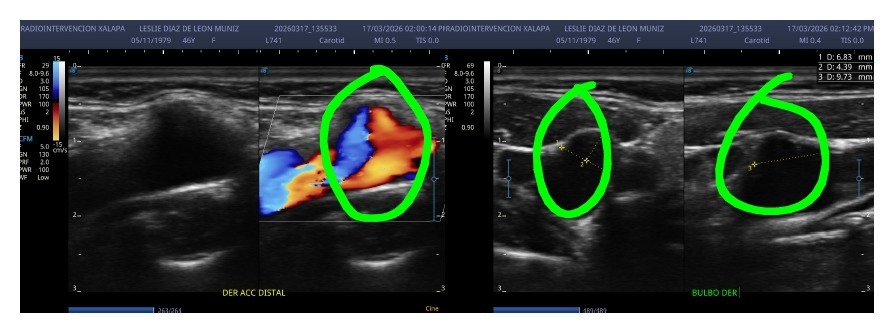

Mi esposa, Leslie Díaz de León Muñiz, fue diagnosticada con un pseudoaneurisma carotídeo, una condición extremadamente grave. Los médicos han sido claros: en cualquier momento puede romperse y provocarle la muerte.